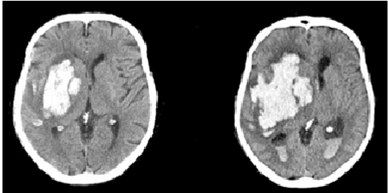

为确定出血的部位和血肿大小,需要进行特殊检查。颅脑CT扫描使脑出血的诊断准确、安全和简便。颅脑CT检查能清楚显示出血部位、血肿大小、出血扩散方向及脑水肿范围,为治疗方案选择提供重要依据。颅脑MRI也能帮助脑出血在短时间内作出准确的诊断。

中老年高血压患者在活动或情绪激动时突然发病,迅速出现偏瘫、失语等局灶性神经功能缺失症状,以及头痛头晕、恶心呕吐及意识障碍等,常高度提示脑出血可能,颅脑CT检查可以确诊。